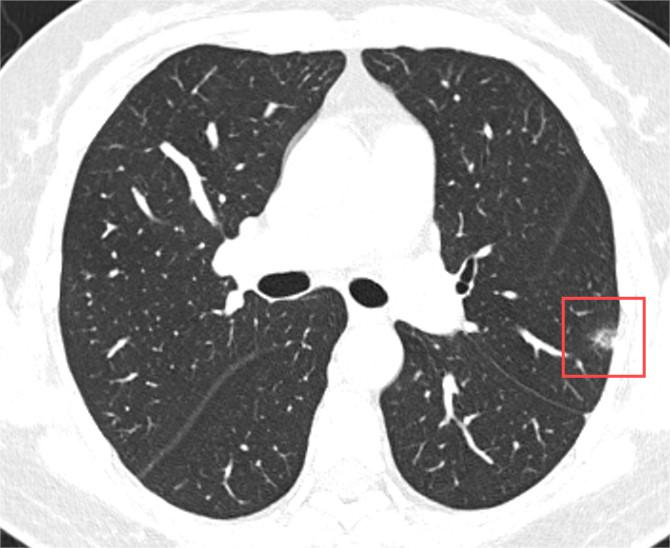

肺小结节通常指的是在肺部CT上直径小于3厘米的圆形或类圆形病灶,它们可以是孤立的,也可以是多发的。与磨玻璃结节不同,肺小结节在CT上的表现更为实质,边界相对清晰。

肺小结节的性质同样多样,包括良性病变(如旧伤、结核球、错构瘤等)和恶性肿瘤。据统计,大多数肺小结节是良性的,只有少数会发展为肺癌。对于肺小结节的管理,同样强调个体化策略,医生会综合考虑结节的大小、形态、患者病史等因素,制定随访计划。一般而言,直径较小的结节建议年度随访。

无论是磨玻璃结节还是普通的肺小结节,其癌变的可能性都不是绝对的。关键在于结节的特性、患者的个体因素以及合理的监测与管理。重要的是,面对肺部结节,我们应保持冷静,避免过度恐慌。